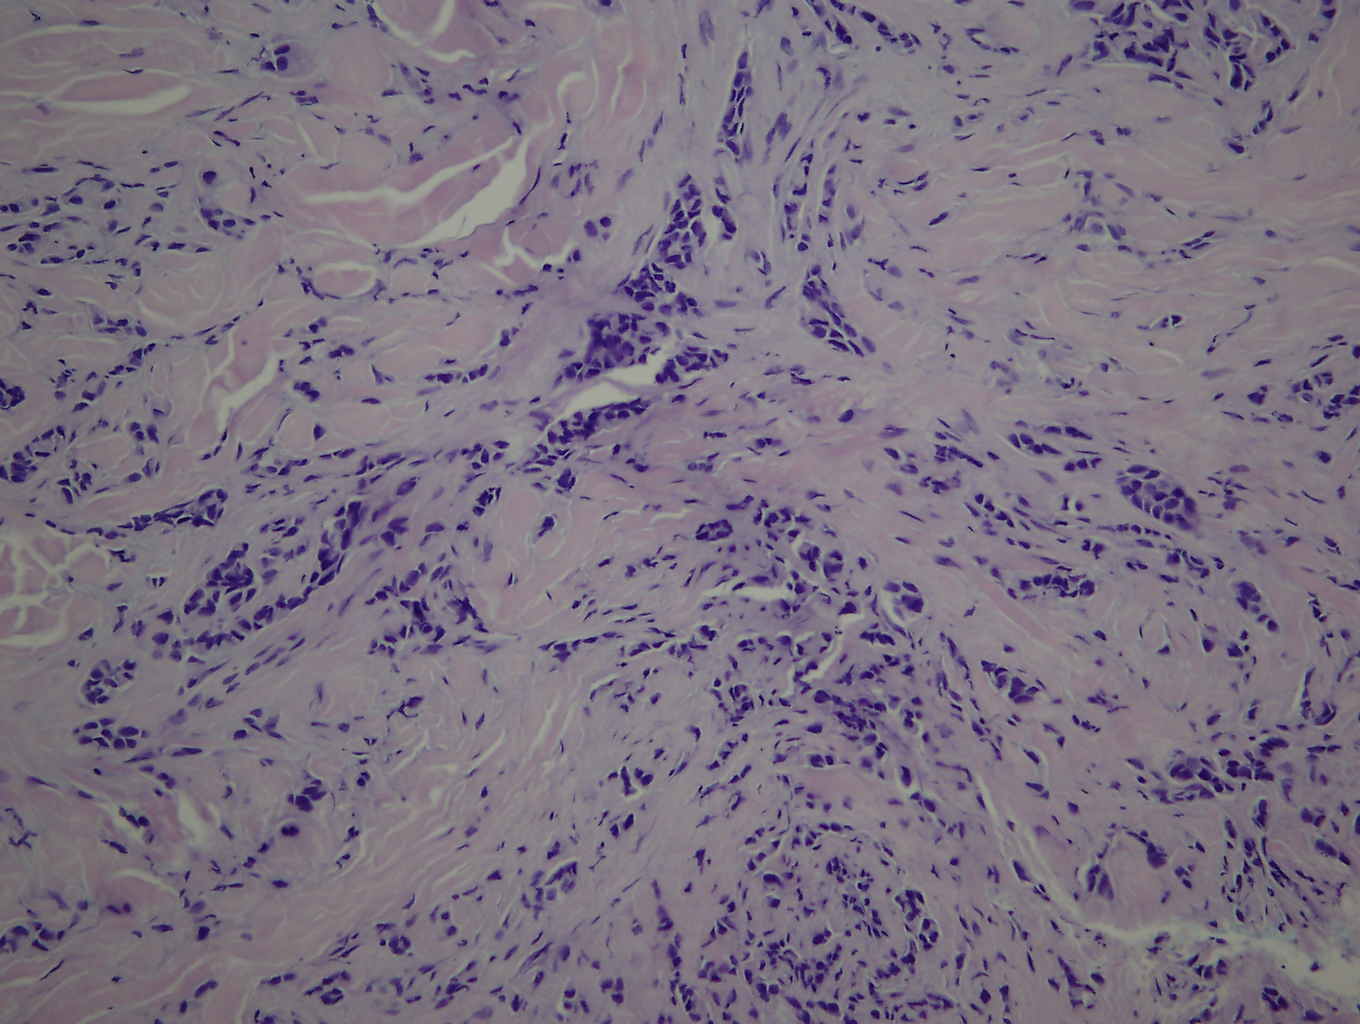

Histopathology of the by opted skin lesion revealed atypical cells that form infiltrative cords, small lobules and ducts throughout the dermis. These cells exhibited marked pleomorphism with high nuclear/ cytoplasmic ratio (Figure 2). Metastatic breast carcinoma was confirmed.

Figure 2 Histopathology: a typical cells that form infiltrative cords, small lobules and ducts throughout the dermis (HE x200).